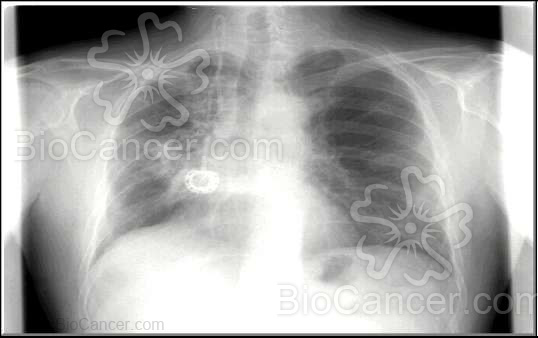

Lesiones viscerales: míocardiopatía (adriamicina); nefropatía (cis-platino); fibrosis pulmonar (busulfán, bleomicina); neumonitis o infiltrados alveolares (methotrexato, gencitabima); cistitis intersticial hemorrágica (ciclofosmamida, ifosfamida). Se trata de toxicidades previsibles, dosis dependiente y en general reversibles, para las que se necesita monitorizar determinadas pruebas analíticas o de imagen que permiten evitar y controlar la toxicidad (ecocardiograma, función renal, espirometría, radiografía de tórax, etc...). Son toxicidades dosis limitante, que en ocasiones no son reversibles y se cronifican con importante deterioro funcional (míocardiopatía o insuficiencia renal con diálisis crónica). la forma y ritmo de perfusión, adecuada hidratación y alcalinización, así como la evaluación clínica en cada ciclo, son las medidas más importantes en el control de la toxicidad visceral.